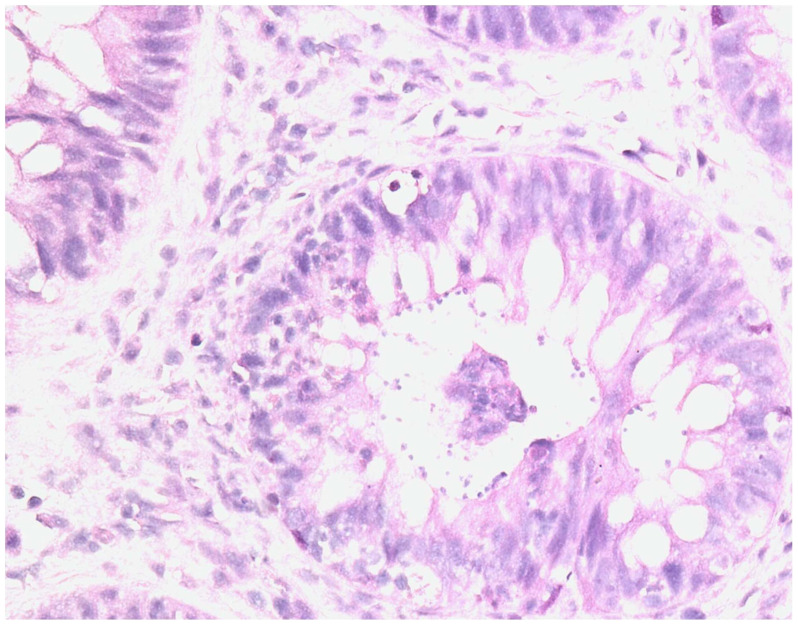

Fecal Microbiota Transplantation as a Salvage Therapy for Concomitant Resistant Digestive Graft Versus Host Disease and Cryptosporidiosis in a Patient Post Hematopoietic Stem Cell Transplant: about a Case.